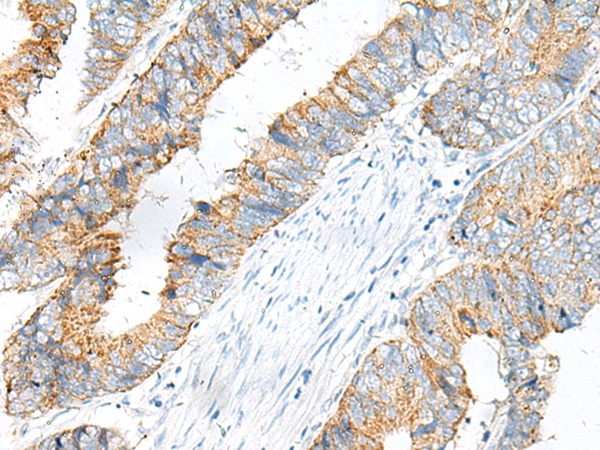

分类: 科研抗体货号: P06610别名: ENA; MENA; NDPP1应用: IHC反应种属: Human, Mouse